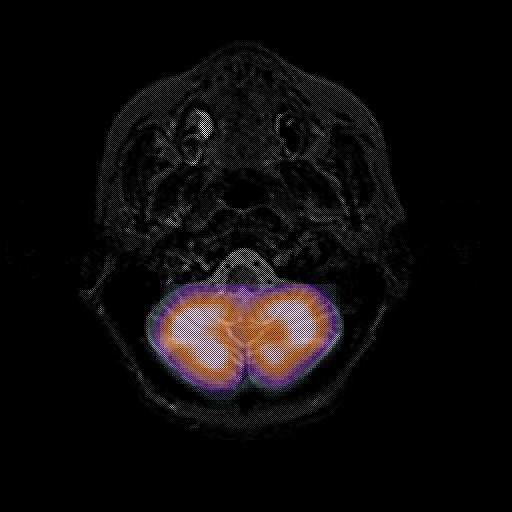

overlay : Slice 8

Slice 8

MRCBFCBF with

T1PDT2T1PDT2